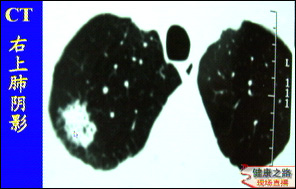

主持人:怎样才能知道自己是否得了肺癌? 王俊:最简单的方法就是到医院做一个体检,其中包括胸片检查,到目前为止胸部X线检查仍然是肺癌的首选筛选检查,如图这位病人在右肺上叶有一个小的结节,然后进行CT检查就是为了明确诊断和分期。近年来肺癌已经成为了人类肿瘤死亡的头号杀手。建议40岁以上有长期吸烟史的人最好每年进行一次体检,以便发现肺癌的早期病变,因为对于晚期肺癌目前医学界还没有很好的解决方法。

主持人:今天所介绍的微创治疗原理是什么? 王俊:从图中可以看出患者的右肺上叶有一个直径2厘米的病灶,可以在胸腔镜下切除掉这个病灶,切下的标本可以送病理检查,在半小时内就可以知道这个肿瘤是良性的还是恶性的。如果是肺癌,肺功能很差,采取这种姑息治疗就可以了,如果患者的肺功能很好,要达到根治治疗的目的就需要再进行根治手术,往往要加一个小的切口,在胸腔镜下就可以很顺利地完成。